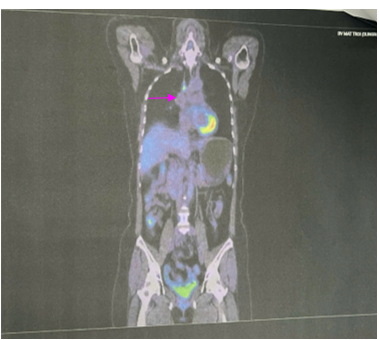

Đánh giá sau 06 chu kỳ Pemetrexed – Carboplatin – Pembrolizumab

PET CT: Hình ảnh nốt mờ bờ tua gai vùng đỉnh phổi phải kích thước 9x12mm; không tăng chuyển hóa FDG. Hạch cạnh khí quản đoạn thấp kích thước 7x9mm, tăng chuyển hóa FDG (SUV max: 4.83). Chưa phát hiện hình ảnh tăng chuyển hóa FDG khu trú, bất thường tại các vị trí khác trên PET CT toàn thân

Hình 8: Hình ảnh PET CT: Hạch cạnh khí quản đoạn thấp kích thước 7x9mm, tăng chuyển hóa FDG (SUV max: 4.83). (mũi tên màu hồng)

Sau 6 chu kỳ Pemetrexed – Carboplatin – Pembrolizumab, đánh giá bệnh đáp ứng; bệnh nhân tiếp tục duy trì Pemetrexed – Pembrolizumab.